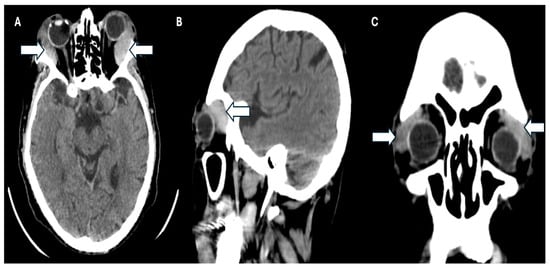

Simultaneously, a simple phase cranial computed axial tomography (CT) scan was requested to continue the approach. This revealed the presence of heterogeneous masses in the upper temporal sector of both orbits at the level of the lacrimal glands and infiltration of the adjacent orbital tissue, causing bilateral proptosis. Additionally, there was evidence of bilateral maxillary sinusitis, with no indication of periorbital cellulitis (Figure 3A–C).

Figure 3. CT scan of the patient. (A) Axial plane, (B) sagittal, and (C) coronal plane where the arrows show infiltration of the adjacent orbital tissue, causing the patient’s bilateral proptosis.